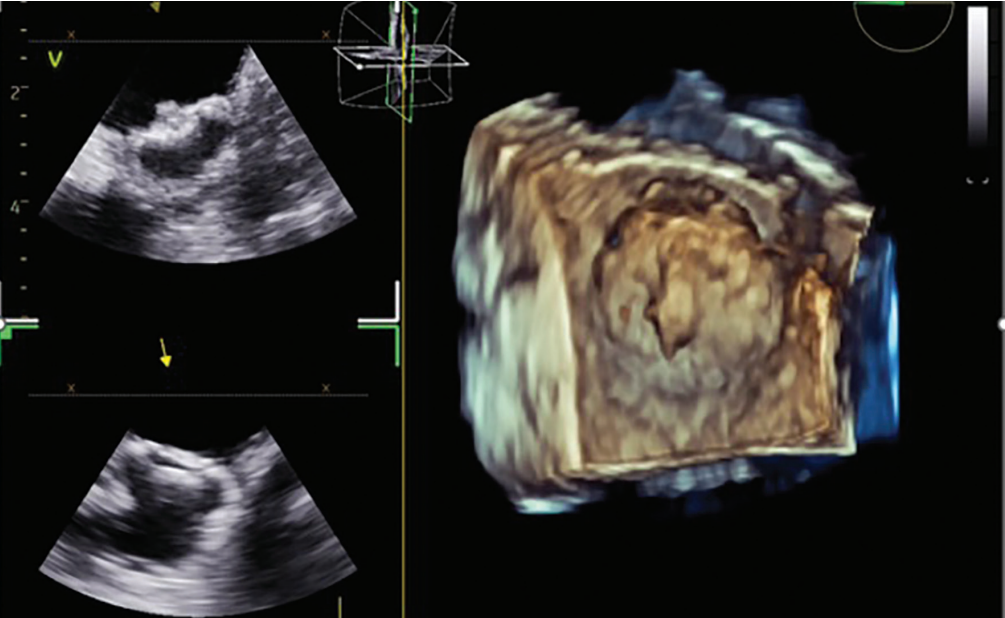

I then transitioned to the 4D ICE NUVISION Ultrasound Catheter and found that it offered superior image resolution with much less catheter manipulation due to the catheter design, as compared to 2D ICE. You can place the catheter in the left atrium in different places, and with minimal manipulation, gather the images that you need in 2D, 3D, and 4D due to its wide imaging field. The ultrasound specialist can provide multiple imaging planes at the same time, so you can quickly and coaxially visualize the device without having to manipulate the catheter. Use of ICE and NUVISION afforded more predictability, more consistent quality, and more control over the imaging, which has facilitated the implant process for me.

It is still common to use ICE for the transseptal and TEE for appendage closure. I think this adds procedural complexity, requires significant coordination, and increases patient discomfort due to the need for a TEE. The use of NUVISION for both procedures gives the electrophysiologist control over imaging quality for PFA and appendage closure. I think we have realized the importance of contact with PFA, not just with respect to lesion efficacy, but also with regard to hemolysis. When placed in the left atrium, NUVISION can be tremendously helpful due to its superior imaging quality and limited need for manipulation. We can clearly assess contact in the pulmonary veins and posterior wall and then use the same catheter for appendage closure. With a single catheter, we can visualize ablation targets and then immediately assess and guide appendage closure—all under one workflow.

I believe NUVISION NAV will be a game changer. I am most excited about CARTOSOUND integration—the ability to see the imaging plane superimposed on a 3D map will improve spatial orientation for both ablation and appendage closure. Remote UI will allow the CARTO clinical to meaningfully integrate ultrasound-guided anatomy with activation mapping. It will make ablation and appendage closure more intuitive for most operators and ensure adequate device imaging. We have data showing that 4D ICE as compared to 2D ICE is associated with fewer device redeployments. You are more likely to get the device in on the first or second try than with 2D if using 4D ICE. So, imaging quality and accuracy can really make a difference when it comes to appendage closure.